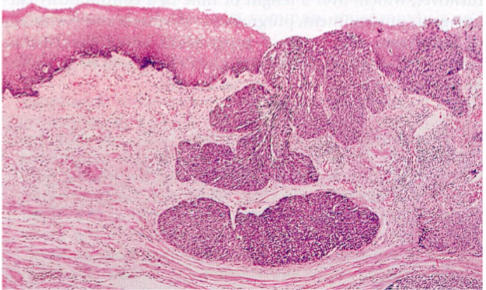

Squamous Carcinoma

Half occur in the middle third of the esophagus

Arise from squamous dysplasia

Squamous: squamous pearls